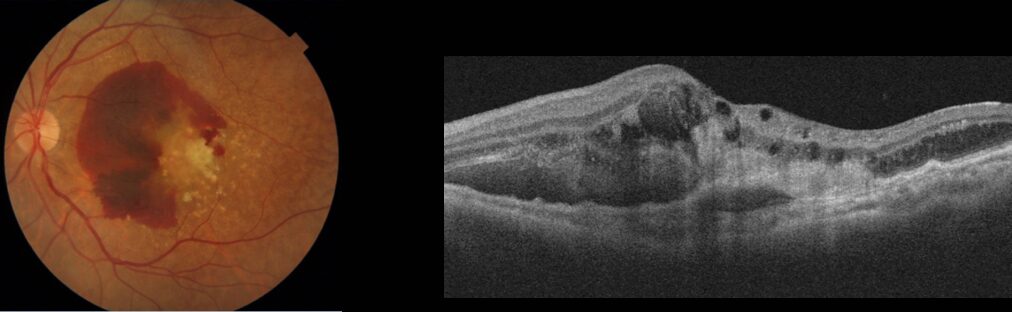

滲出型

新生血管が出来て、そこから出血したり、液体成分が流れ出したりすることで黄斑部にむくみが出ることが多いです。日本人の患者さんの約9割がこのタイプです。進行が比較的速く、見つかった時点ですぐ治療をする必要があります。